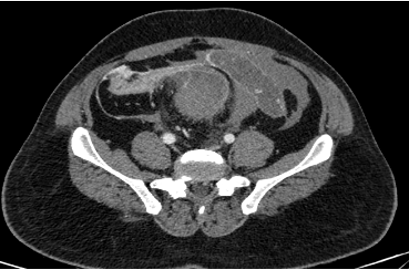

• X-ray showing prominent soft tissue shadow at the level of proximal 1/3rd humeral shaft region. No bony abnormality.

• A large altered signal intensity soft tissue lesion arising from the diaphysis of mid shaft region of humerus in posterior aspect with shallow surface cortical erosions, and spiculated periosteal reaction.

• The lesion demonstrates T2/STIR heterogeneous hyperintense signal and T1 hypointense signal with few cystic spaces. Multiple flow voids noted within lesion ( *). Mild intramedullary edema however no intramedullary extension.